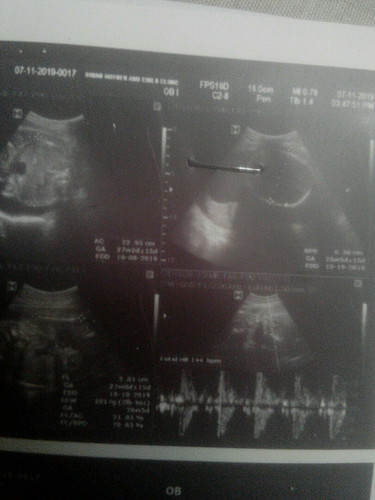

sino po pwd mag explain or makapagsabe po sken kung ano ung result ng ultrasound ko. if Normal po ba at healthy naman si baby

26weeks & 6days pregnant po ako. hnd pa din malaman kung anong gender ni bby. nakaharang daw po kse ung buto or pwet ata. hina kse ng boses nung nag uultrasound ?